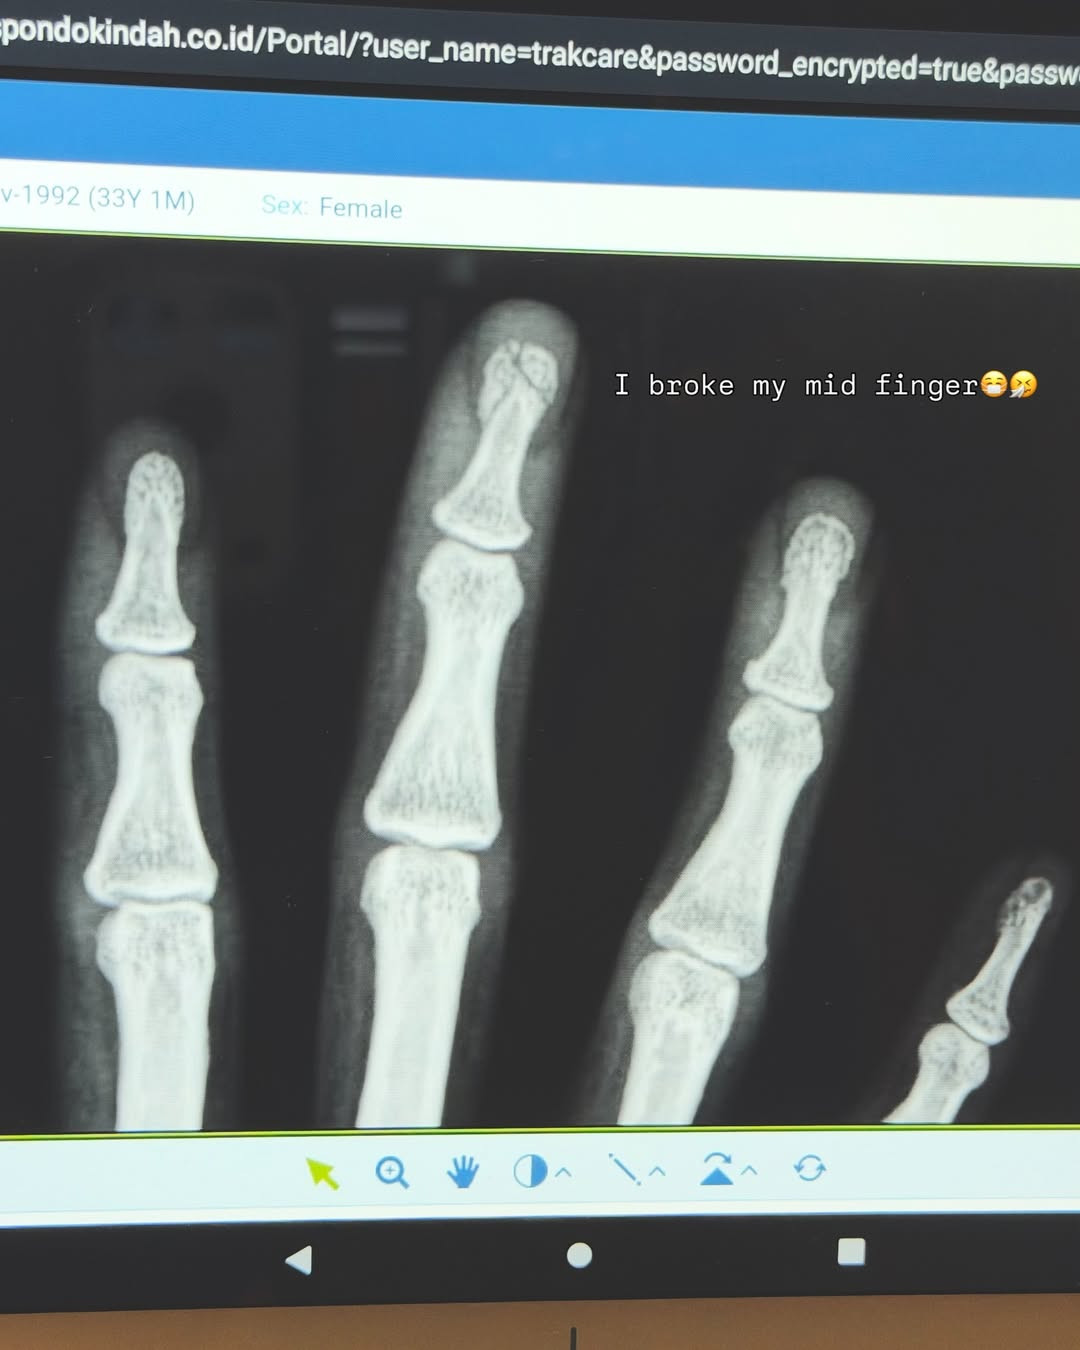

Tak hanya itu, ia juga menyertakan foto hasil rontgen yang memperlihatkan adanya retakan di ujung jari tengah tangannya.

"I broke my mid finger (aku mematahkan jari tengahku)," ujarnya, disusul kalimat, "Gotta end the year with a plot twist, right? (harus menutup tahun dengan kejutan tak terduga, kan?)."